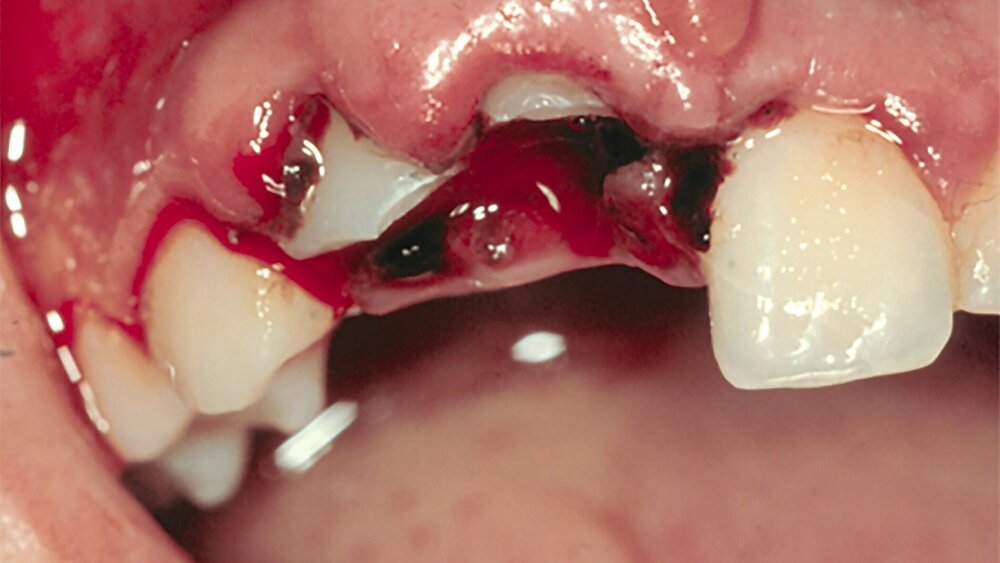

Extrusionstraumata betreffen gerne Zähne vor Ende des Wurzelwachstums. Sie können mit großen Blutkoageln behaftet sein, die eine unstillbare Blutung vortäuschen. In Wahrheit lockert der weit aus der Alveole ragende und durch Lippen- und Zungendruck bewegte Zahn laufend das Blutkoagel und verhindert dadurch die Hämostase. Nach Reposition und Schienung findet sich ein Bild, das der traumatischen Lockerung entspricht. Die Sensibilität ist negativ und es ist keine Perkussionsempfindlichkeit feststellbar.

Zur Dokumentation wird auch die Erstellung klinischer Fotos im Rahmen der Erstversorgung vor Therapiebeginn empfohlen. Gerade bei Dislokationsverletzungen geben Fotos oft wichtige Hinweise auf die Art und den Schweregrad der Zahnverlagerung, was maßgeblichen Einfluss darauf hat, ob eine endodontische Behandlung initiiert werden muss. Diese Information ist nach der Repositionierung des Zahnes nicht mehr vorhanden und kann auch auf dem Röntgenbild oftmals nicht genau beurteilt werden. Im optimalen Fall werden vor der Erstversorgung auf dem Behandlungsstuhl hochwertige Dentalaufnahmen von labialer und inzisaler Richtung aufgenommen. Gleichwohl können auch selbst erstellte Fotos oder Selfies wertvolle Informationen liefern. Neben der forensischen Dokumentation ist es durch Bildmaterial vom Unfalltag auch möglich, Zahnverfärbungen oder die Heilung von Weichgewebswunden nachzuvollziehen (Abbildung 6). Im Zuge der Nachkontrollen erleichtern fotografische Aufnahmen zudem die Feststellung von Infrapositionen bei Ankylosen oder die spontane Eruption bei Intrusionsverletzungen.

Die Fotodokumentation stellt eine hilfreiche Technik dar, da sie eine Ergänzung der Befunde erlaubt und die Klassifikation der Art des Traumas erleichtern kann. Sie sollte vor allem aus forensischen Gründen (Haftungs-Gesichtspunkte) eingesetzt werden und von labial und von inzisal am Unfalltag vor der weiteren Therapie erfolgen (Empfehlung 6).